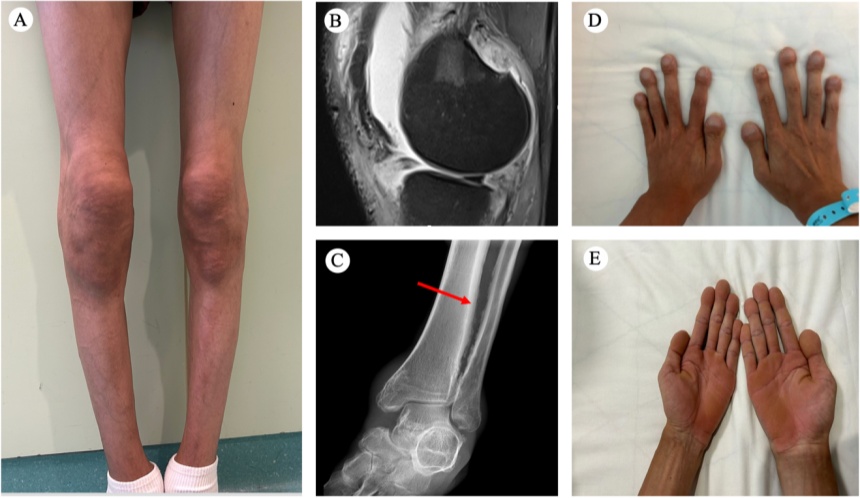

经全外显子基因测序及家系验证,患者被确诊为携带HPGD基因复合杂合剪切突变。该突变导致前列腺素E2(PGE2)的降解发生异常,从而引发前列腺素E2异常蓄积、产生关节肿痛。PHO的经典临床表现为杵状指、骨膜增生、关节肿胀和掌跖角化病(图1),其核心发病机制为HPGD或SLCO2A1基因突变介导的前列腺素E2降解障碍及其蓄积。

图1:(A)膝关节肿胀及肿大 (B)磁共振成像显示滑膜增生 (C)胫腓骨X线显示骨膜增生(红色箭头所示) (D)杵状指 (E)掌跖角化